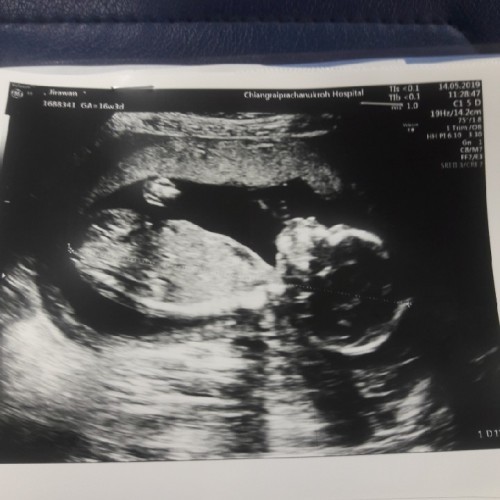

ผู้ชายครับ 35w แล้ว